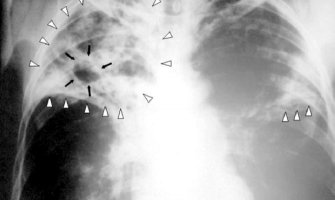

Američki naučnici s Univerziteta Nju Meksiko razvili su prvi test za otkrivanje tuberku...

Američki naučnici Univerziteta Nju Meksiko razvili su prvi test za otkrivanje tuberkulo...